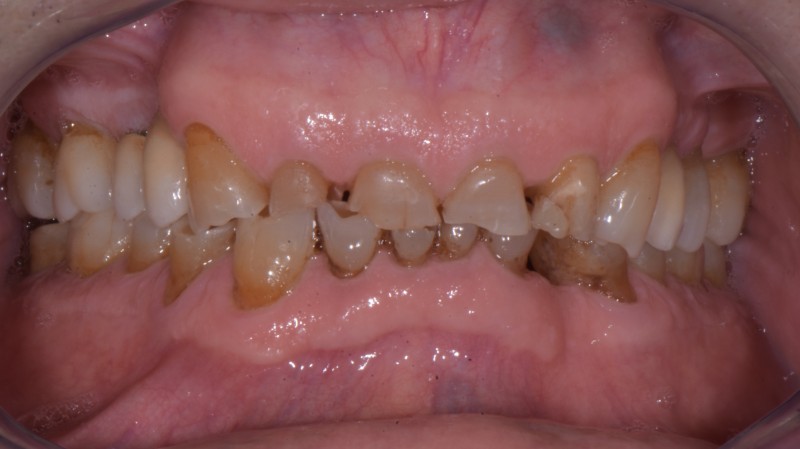

Prima e dopo il trattamento

Trascina il cursore per confrontare il risultato ottenuto.

Dopo il trattamento Prima del trattamento

Ortodonzia con mascherine trasparenti

Ortodonzia invisibile

Paziente: Donna, 17 anni